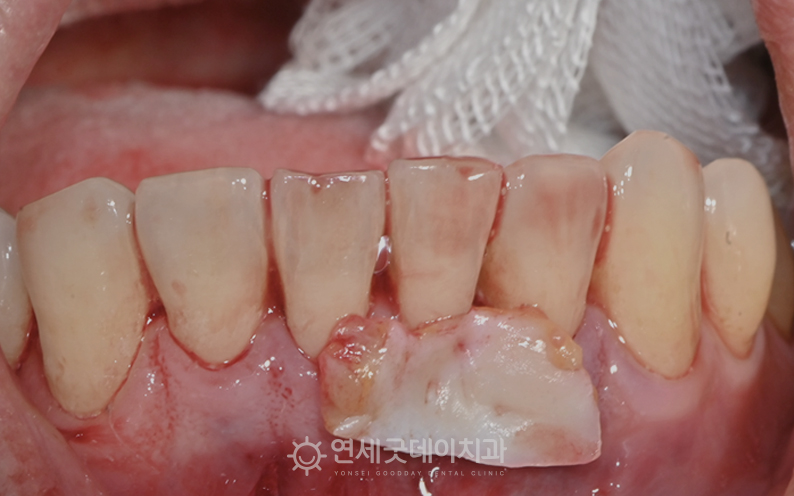

▲ 아랫니부분교정 종결 후 핀홀 과정 (촬영시기 : 2025년 9월)

입천장에서 채취한 잇몸조직과